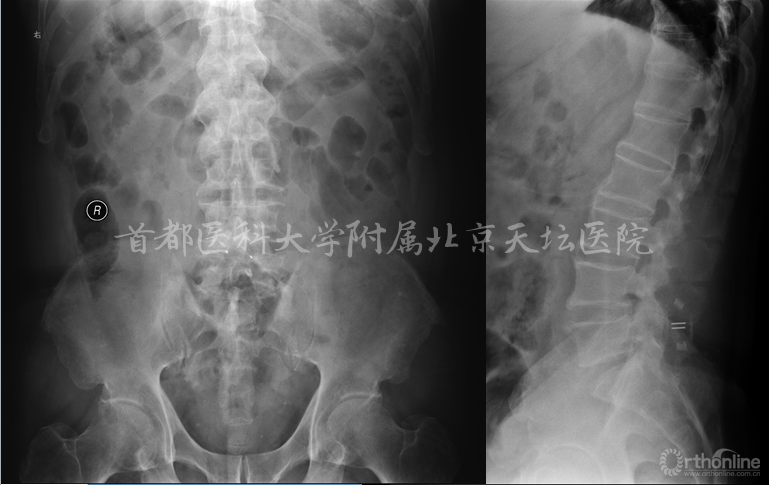

影像资料:

脊髓型颈椎病、颈椎间盘突出症、腰4滑脱(l度)、腰椎管狭窄、高血压病、冠心病。

本例影像学检查结果示C3-4,C5-6及C6-7均有硬膜囊受压,但是结合症状、体征、高龄,我们选择C5-6为责任节段,进行了针对性的减压,取得了良好的效果。